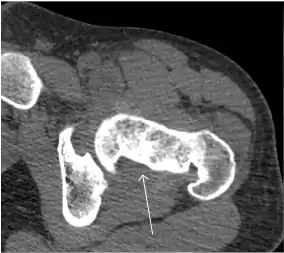

Synovial chondromatosis can be confidently diagnosed by X-ray when calcified cartilaginous chondromas are seen. However, other synovial proliferative processes, such as pigmented villonodular synovitis, require MRI for accurate diagnosis, although noncalcified synovitis can be suspected in radiographs by indirect signs, such as soft tissue swelling and/or erosions in the femoral head, femoral neck, or acetabulum (Figure 7).[1]

Figure 7:

Axial CT image of pigmented villonodular synovitis eroding the posterior cortex of the femoral neck.[1]

Sagittal T2* gradient echo image showing a posterior soft tissue mass with hypointense areas secondary to hemosiderin deposition.[1]

X-ray of synovial chondromatosis.[1]

CT of synovial chondromatosis.[1]

In synovial proliferative disorders, MRI demonstrates synovial hypertrophy. In the case of PVNS, characteristic foci of low signal intensity related to hemosiderin deposition are better seen on gradient echo T2* images (Figure 7). In the case of synovial osteochondromatosis, the synovial hypertrophy is accompanied by intermediate signal cartilaginous loose bodies and/or low signal calcified loose bodies.[1]

Computed Tomography

Due to radiation concerns, CT has been relegated after MRI in the study of intra-articular causes of hip pain. The only exception where CT is considered superior to MRI is in bone tumors, because of its ability in characterizing matrix calcifications, and in depicting the anatomy of acute traumatic fractures. Typical matrix calcifications include the following: (a) osteoid mineralization, like a dense cloud, (b) chondroid calcification, reproducing a punctate popcorn pattern, or (c) fibrous calcification, ground glass-like appearance. There are also tumors that typically do not show matrix calcification. CT is also used for accurate localization of the nidus in osteoid osteomas and this must be differentiated from Brodie’s abscess or a stress fracture. The current standard treatment of osteoid osteoma is percutaneous radiofrequency ablation and this is usually performed under CT guidance.[1]